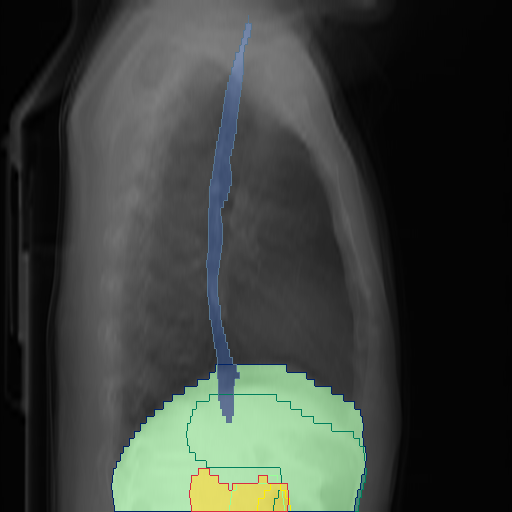

We show qualitative results for frontal projections in Fig. 2. We show a subset of classes belonging to the supercategories lungs, vascular systems, bones, and abdomen/digestive system. The predictions show minor deviations at the boundaries of the individual classes of the respiratory and vasculature system, while some inaccuracies become visible in the abdominal area. The qualitative results for the lateral projections are displayed in Fig. 2. Akin to the frontal view, the predictions show smoother borders but align with the ground truth. Apart from this, the segmentations provide matching insights on the thoracic anatomy with a slight deviation from the ground truth for both frontal and lateral views.

We display qualitative results in Fig. 3. The annotators tend to be content with most annotations. There are edits at the extensions of the esophagus, trachea, and aorta and corrections of the lower ribs. There is little consensus for classes in the abdominal area, such as the stomach, as seen on the right of Fig. 3 . In contrast, the annotators often align for bone classes.